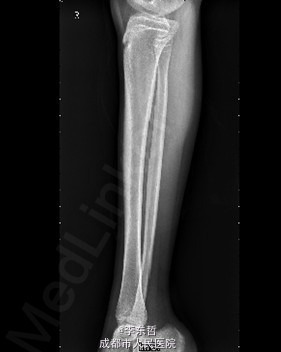

查体:右足内踝、外踝及跟部皮肤变暗,部分缺血坏死。未见畸形,稍肿胀。触:右足趾皮温无明显降低,右足趾感觉未见明显异常。右足内踝、外踝及跟部皮肤局部压痛。动量:右踝关节活动受限,右踝关节活动诱发疼痛。右膝关节活动未见明显异常。 辅助检查:X线示:右跟骨骨折,右胫骨远端骨折。

初步诊断:1、右足跟部皮肤软组织撕脱伤清创缝合术后皮肤软组织大面积坏死伴感染;2、右跟骨骨折;3、右胫骨远端骨折;4、右足跖屈畸形。 处理:1、向患者及家属交待病情及注意事项。2、向上级医生汇报患者病情。3、完善相关术前等检查,择期行手术治疗。4、给予对症支持治疗。5、密切观察病情变化,根据病情及时处理。